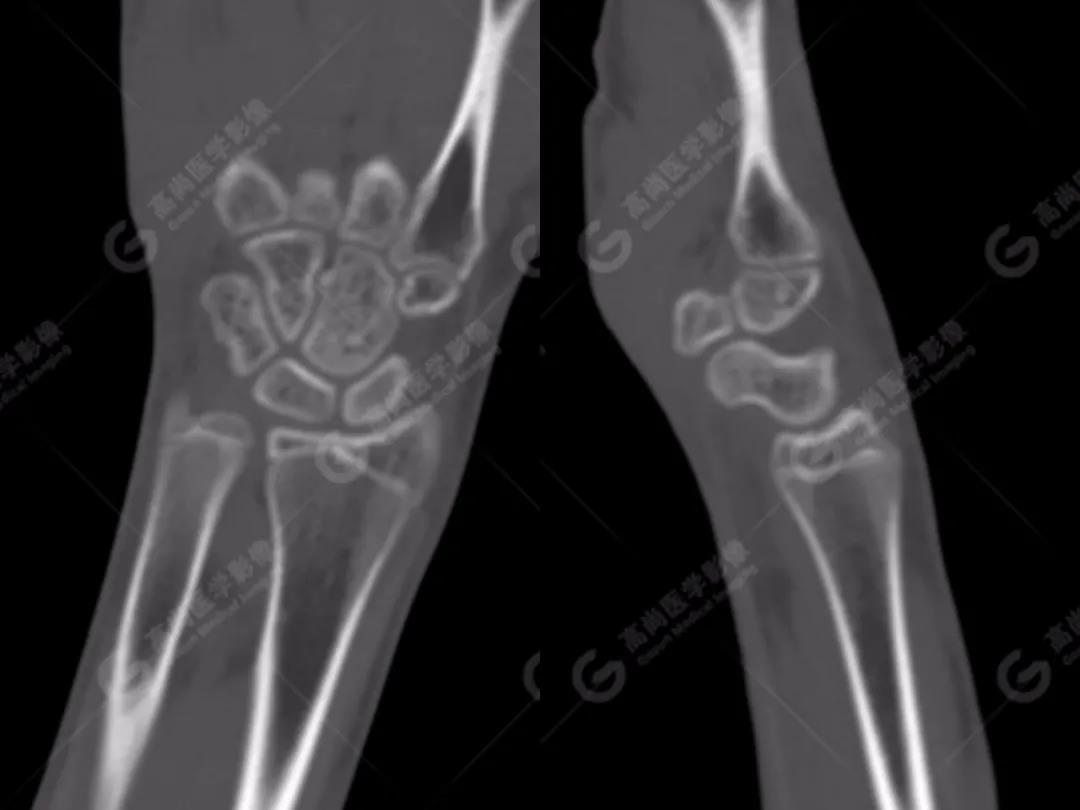

2、常規(guī)CT圖像

常規(guī)CT平掃灰階圖像上雙腕關(guān)節(jié)仍然未見明顯骨折征象。